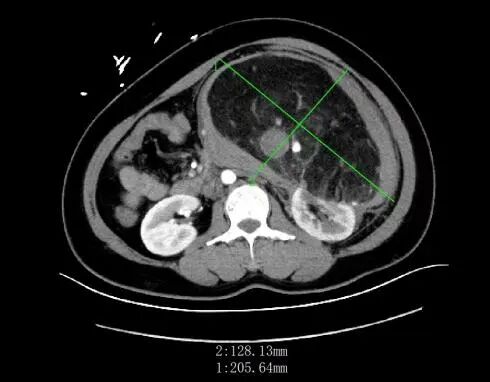

前一段時間,家住惠城區(qū)的林女士(化名)突發(fā)腹痛嘔吐,由120送至惠州市第三人民醫(yī)院急診科。完善全腹部CT后,醫(yī)生發(fā)現(xiàn)患者左腎存在一個巨大腫瘤,直徑約20cm,并伴有破裂出血。

左腎巨大腎錯構瘤約20*20*13cm

隨著超聲檢查在體檢中普及,超過一半的偶發(fā)腎錯構瘤在體檢中被發(fā)現(xiàn),隨后經CT或MRI確診。比如林女士,她的腹部增強CT中可見明顯強化的血管結構和無強化的脂肪組織。